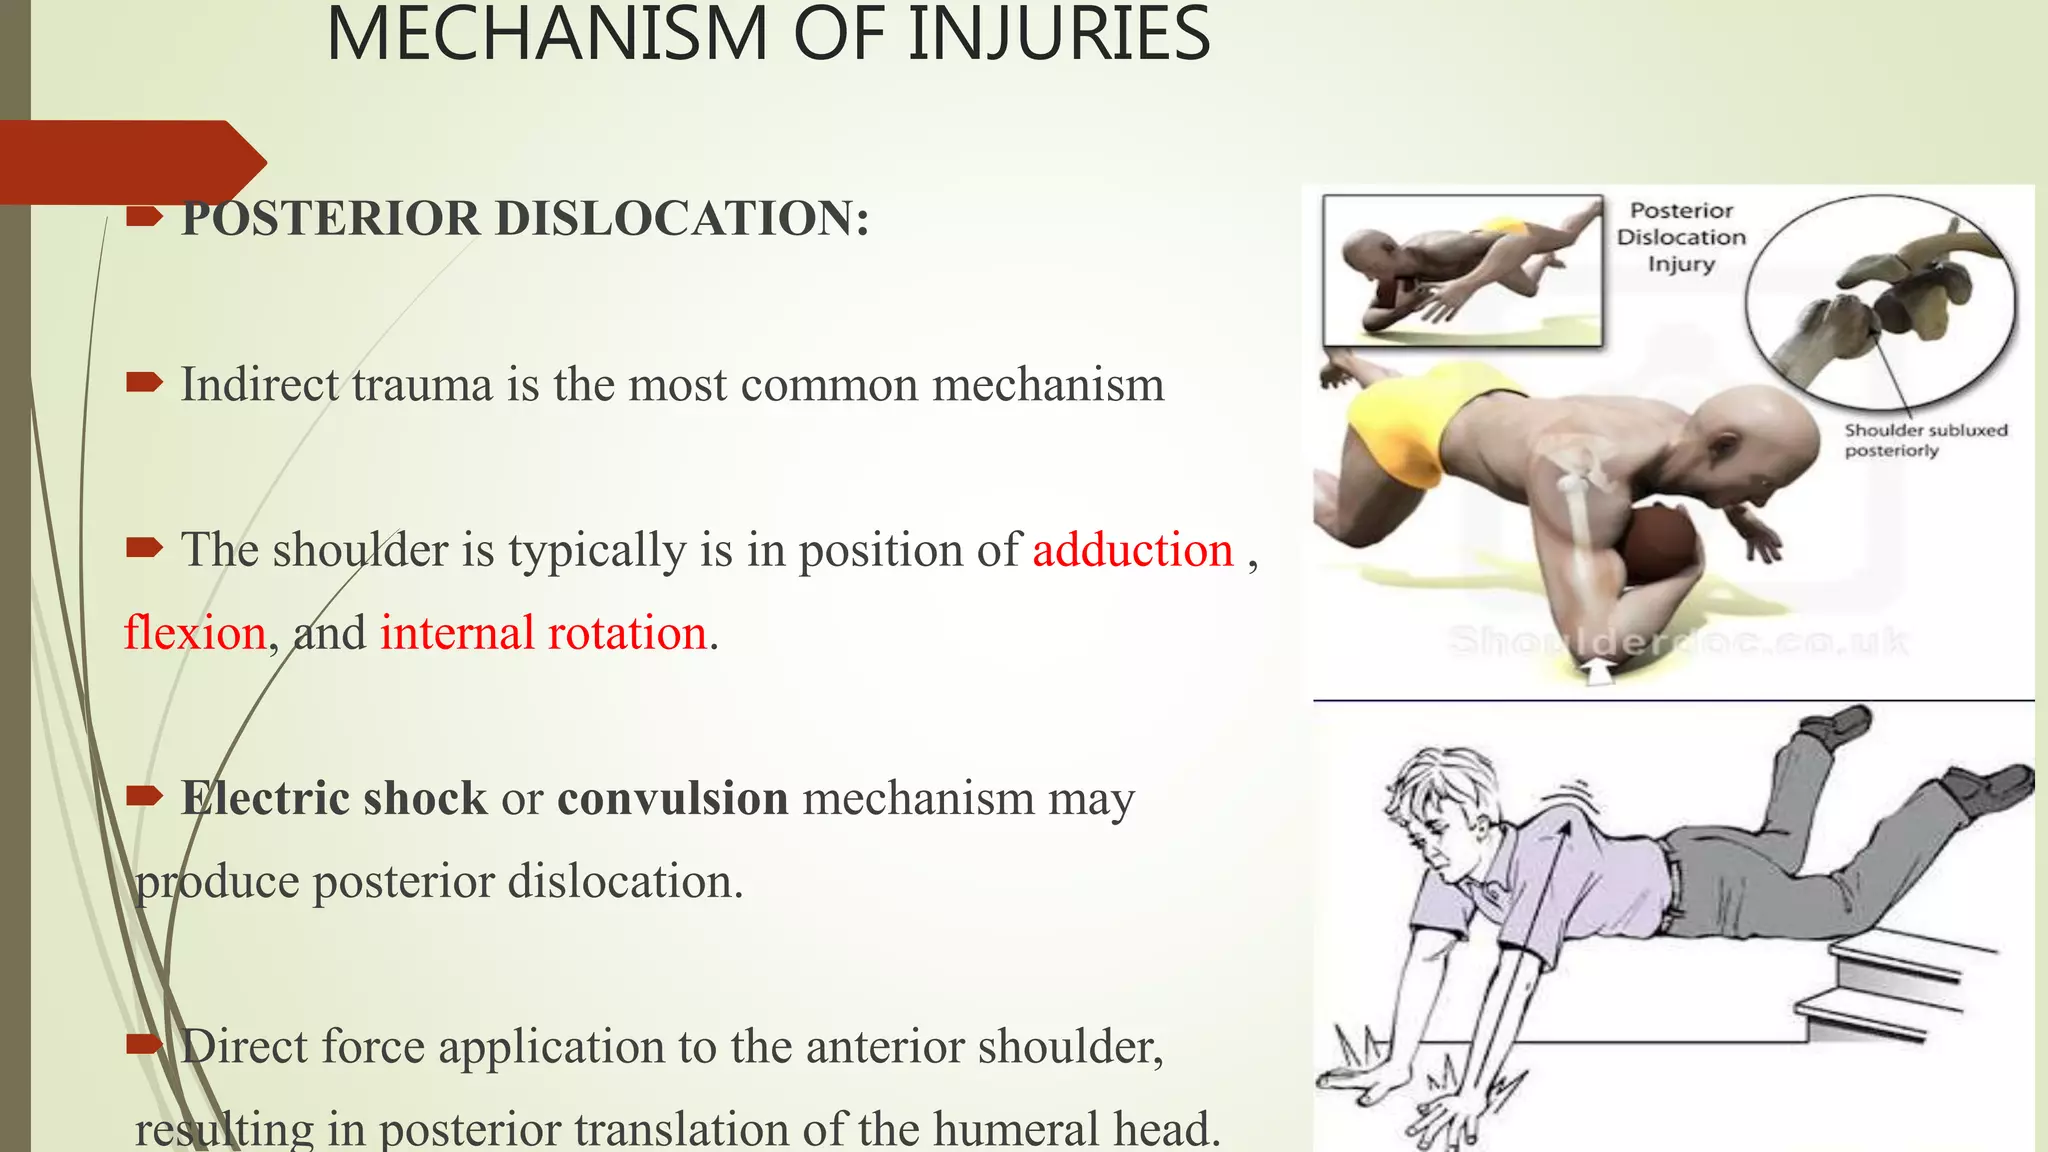

- Shoulder dislocations are commonly caused by trauma that places the shoulder in positions of extreme range of motion. Anterior dislocations are the most common type.